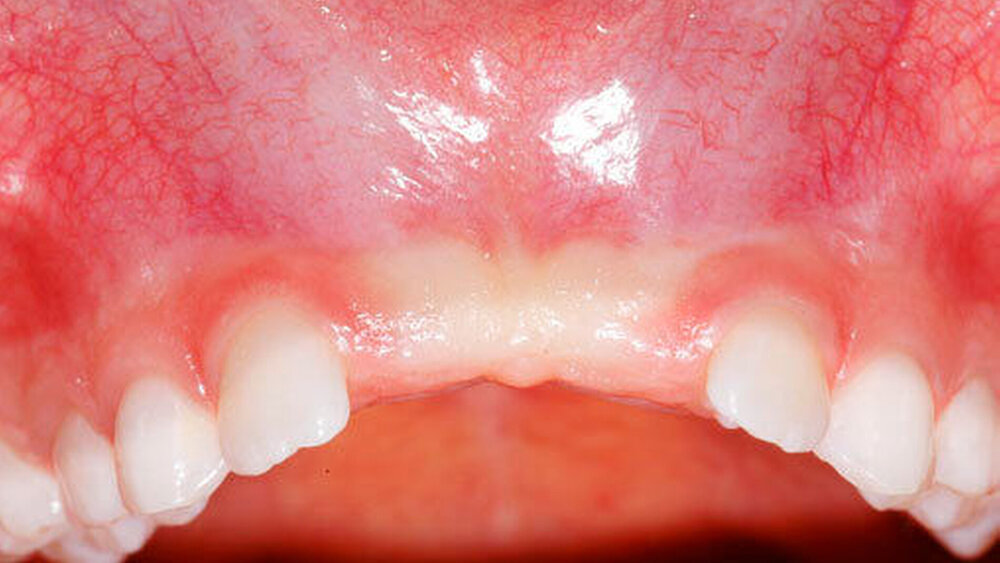

Die Prävalenz überzähliger Zähne wird im Bereich von 0,07 Prozent bis 0,6 Prozent für das Milchgebiss [Luten, 1967; Ravn, 1971; Järvinen Lehtinen, 1981; Magnússon 1984; Skrinjari Barac-Furtinovi, 1991; Yonezu et al., 1997; Chen et al., 2010] und von 0,3 Prozent bis 3,2 Prozent für die bleibenden Zähne [Luten, 1967; Bäckman Wahlin, 2001; Salcido-García et al., 2004; Leco Berrocal et al., 2007; Gündüz et al., 2008; Yagüe-García et al., 2009; Schmuckli et al., 2010; Fardi et al., 2011] angegeben. Die Mehrheit der überzähligen Zähne im Milchgebiss sind seitliche Schneidezähne im Oberkiefer, die meist mit einer normalen Morphologie und Lage durchbrechen (Abbildungen 1 bis 3) [Luten, 1967; Humerfeld et al., 1985; Garvey et al., 1999; Ferrés-Padró et al., 2009]. Der oft ungestörte Durchbruch und das Ausbleiben von Symptomen führen dazu, dass überzählige Zähne in der Milchdentition oft gar nicht diagnostiziert werden, und dies wird auch als Erklärung für die unterschiedlichen Prävalenzen überzähliger Zähne im Milch- und bleibendem Gebiss angeführt [Wang Fan, 2011]. Überzählige Zähne sind häufiger bei Männern als bei Frauen, wobei über ein Verhältnis von 1,18:1 bis 4,5:1 berichtet wird [Rajab Hamdan, 2002; Fernández Montenegro et al., 2006; Gündüz et al., 2008; Wang Fan, 2011]. In der Schweiz publizierten von Arx (1990) und Schmuckli und Mitarbeiter (2010) Geschlechterverhältnisse von 2,6:1, beziehungsweise 2,75:1. In einer aktuellen Arbeit von Mossaz und Mitarbeiter (2014) von Patienten aus dem Raum Bern lag dieses Verhältnis etwas ausgeglichener bei 1,61 zu 1.

Bei überzähligen Zähnen werden vier morphologische Typen unterschieden: konisch (Abbildung 9), tuberkulär (höckerförmig; Abbildung 10), überzählige Zähne mit identischer Zahnform (Abbildung 11) und Odontom (Abbildung 12) [GARVEY et al. 1999]. Der konische überzählige Zahn ist ein kleiner, zapfenförmiger Zahn und zudem der häufigste Fall im bleibenden Gebiss [Rajab Hamdan 2002, Liu et al. 2007, Gündüz et al., 2008; Ferrés-Padró et al., 2009; Hyun et al., 2009; Schmuckli et al., 2010; Mossaz et al., 2014]. Er kommt oft zwischen den oberen zentralen Schneidezähnen vor und entwickelt sich gleichzeitig zur Wurzelbildung der bleibenden Schneidezähne. Konische überzählige Zähne führen meist nicht zu einer Durchbruchstörung oder -behinderung der zentralen Schneidezähne. Tuberkuläre, überzählige Zähne sind größer als der konische Typ und besitzen einen zusätzlichen charakteristischen Höcker oder Tuberkel der Zahnkrone. Sie kommen oft gepaart vor und liegen in der Regel palatinal der oberen mittleren Schneidezähne. Im Gegensatz zu konischen überzähligen Zähnen brechen die meisten tuberkulären nicht in die Mundhöhle durch und es kommt nicht selten zur Durchbruchstörung oder -behinderung der zentralen Schneidezähne [Mason et al., 2000; Minguez-Martinez et al., 2012]. Überzählige Zähne mit identischer Zahnform sind Zähne, welche vom eigentlichen Zahn in der Lage (also in der Zahnreihe gelegen) und Form nicht zu unterscheiden sind.

Die überzähligen Zähne mit identischer Zahnform finden sich normalerweise beim oberen seitlichen Schneidezahn. Zusätzliche Prämolaren und Molaren können aber auch auftreten. Die Mehrheit der überzähligen Zähne im Milchgebiss sind vom identischen Zahnform-Typ und bleiben nur selten impaktiert oder retiniert.